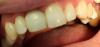

METT Опубликовано 26 апреля, 2013 Автор Поделиться Опубликовано 26 апреля, 2013 (изменено) 45-кариес 5 класс,кариес дистально,две небольшие изолированные полости,пломба дистально и щечно,полировка Изменено 26 апреля, 2013 пользователем METT Ссылка на комментарий